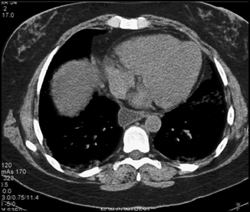

Pulmonary Infarct